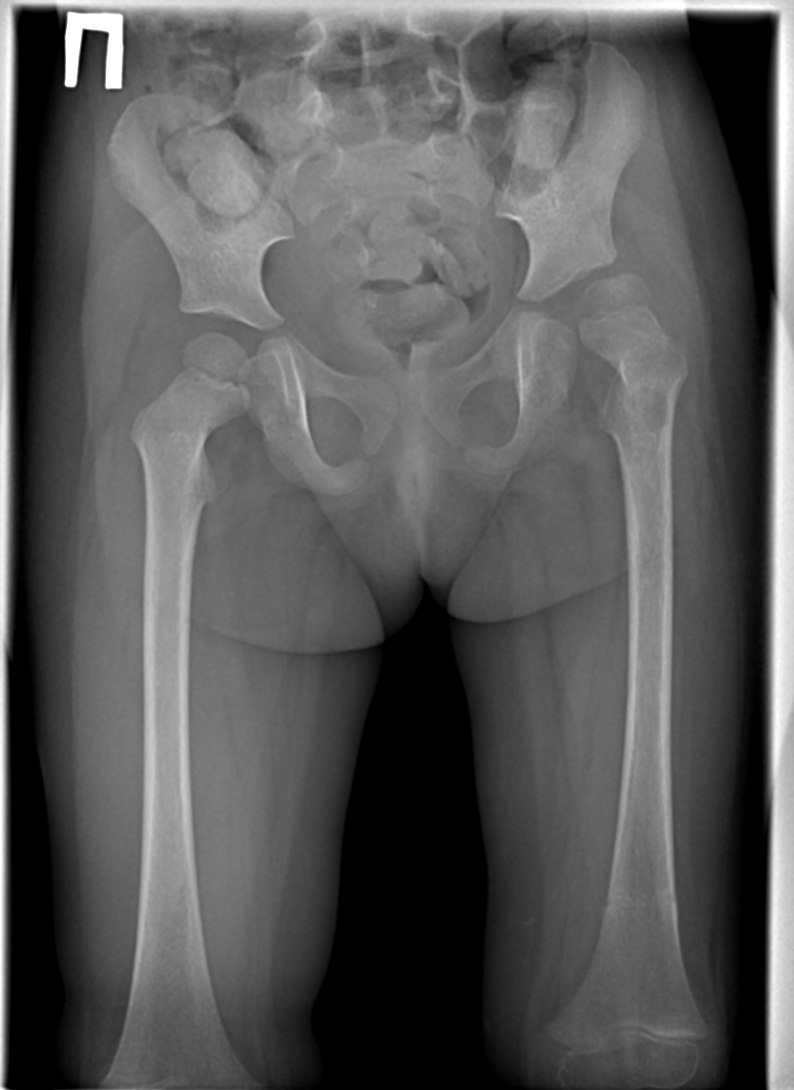

Пациентка,9 лет контроль, лечения остеомиелита. На первом снимке нестабильности не вижу, на втором снимке вижу подвывих ТБС( ассиметричная укладка?). Разница в снимках месяц,травмы за этот месяц не было. Как вы считаете подвывих вследствие врожденной дисплазии?(хирургии говорят что в анамнезе о дисплазии не знают,пациентку я не видел)  К сожелению в детской рентгенологии,плаваю еще болше чем взрослой..

Признаков дисплазии не нахожу. Крыши вертлужных впадин хорошо выражены, не скошены. На первом снимке головки центрированы в вертлужных впадинах. На контрольных, действительно, появился подвывих головки левого бедра. Головка левого бедра, шейка, область вертелов порозны, с округлыми, неправильной формы и нечеткими контурами просветлениями. На контрольном снимке головка деформирована, уплощена. В заключении написала бы признаки остеомиелита.

К остемиелиту ( известному хирургам) - вывих левого тазобедренного сустава, динамика отрицательная. Конечно, укладка на 1-ом снимке плохая, но диагноз без вопросов. Несмотря на " нескошенность" вертлужной впадины - смотрим головку. Середина проксимального эпифиза левой бедренной кости ЗА краем вертлужной впадины. :-(

Так ведь уже и на первом снимке признаки остеомиелита имеются, подвывих бедра - его следствие. Усугубился со временем.

Середина головки не будет за краем по первому снимку, если расчертить по нему. Она, возможно, оказалась бы за ним, если бы в нужной укладке он был выполнен.